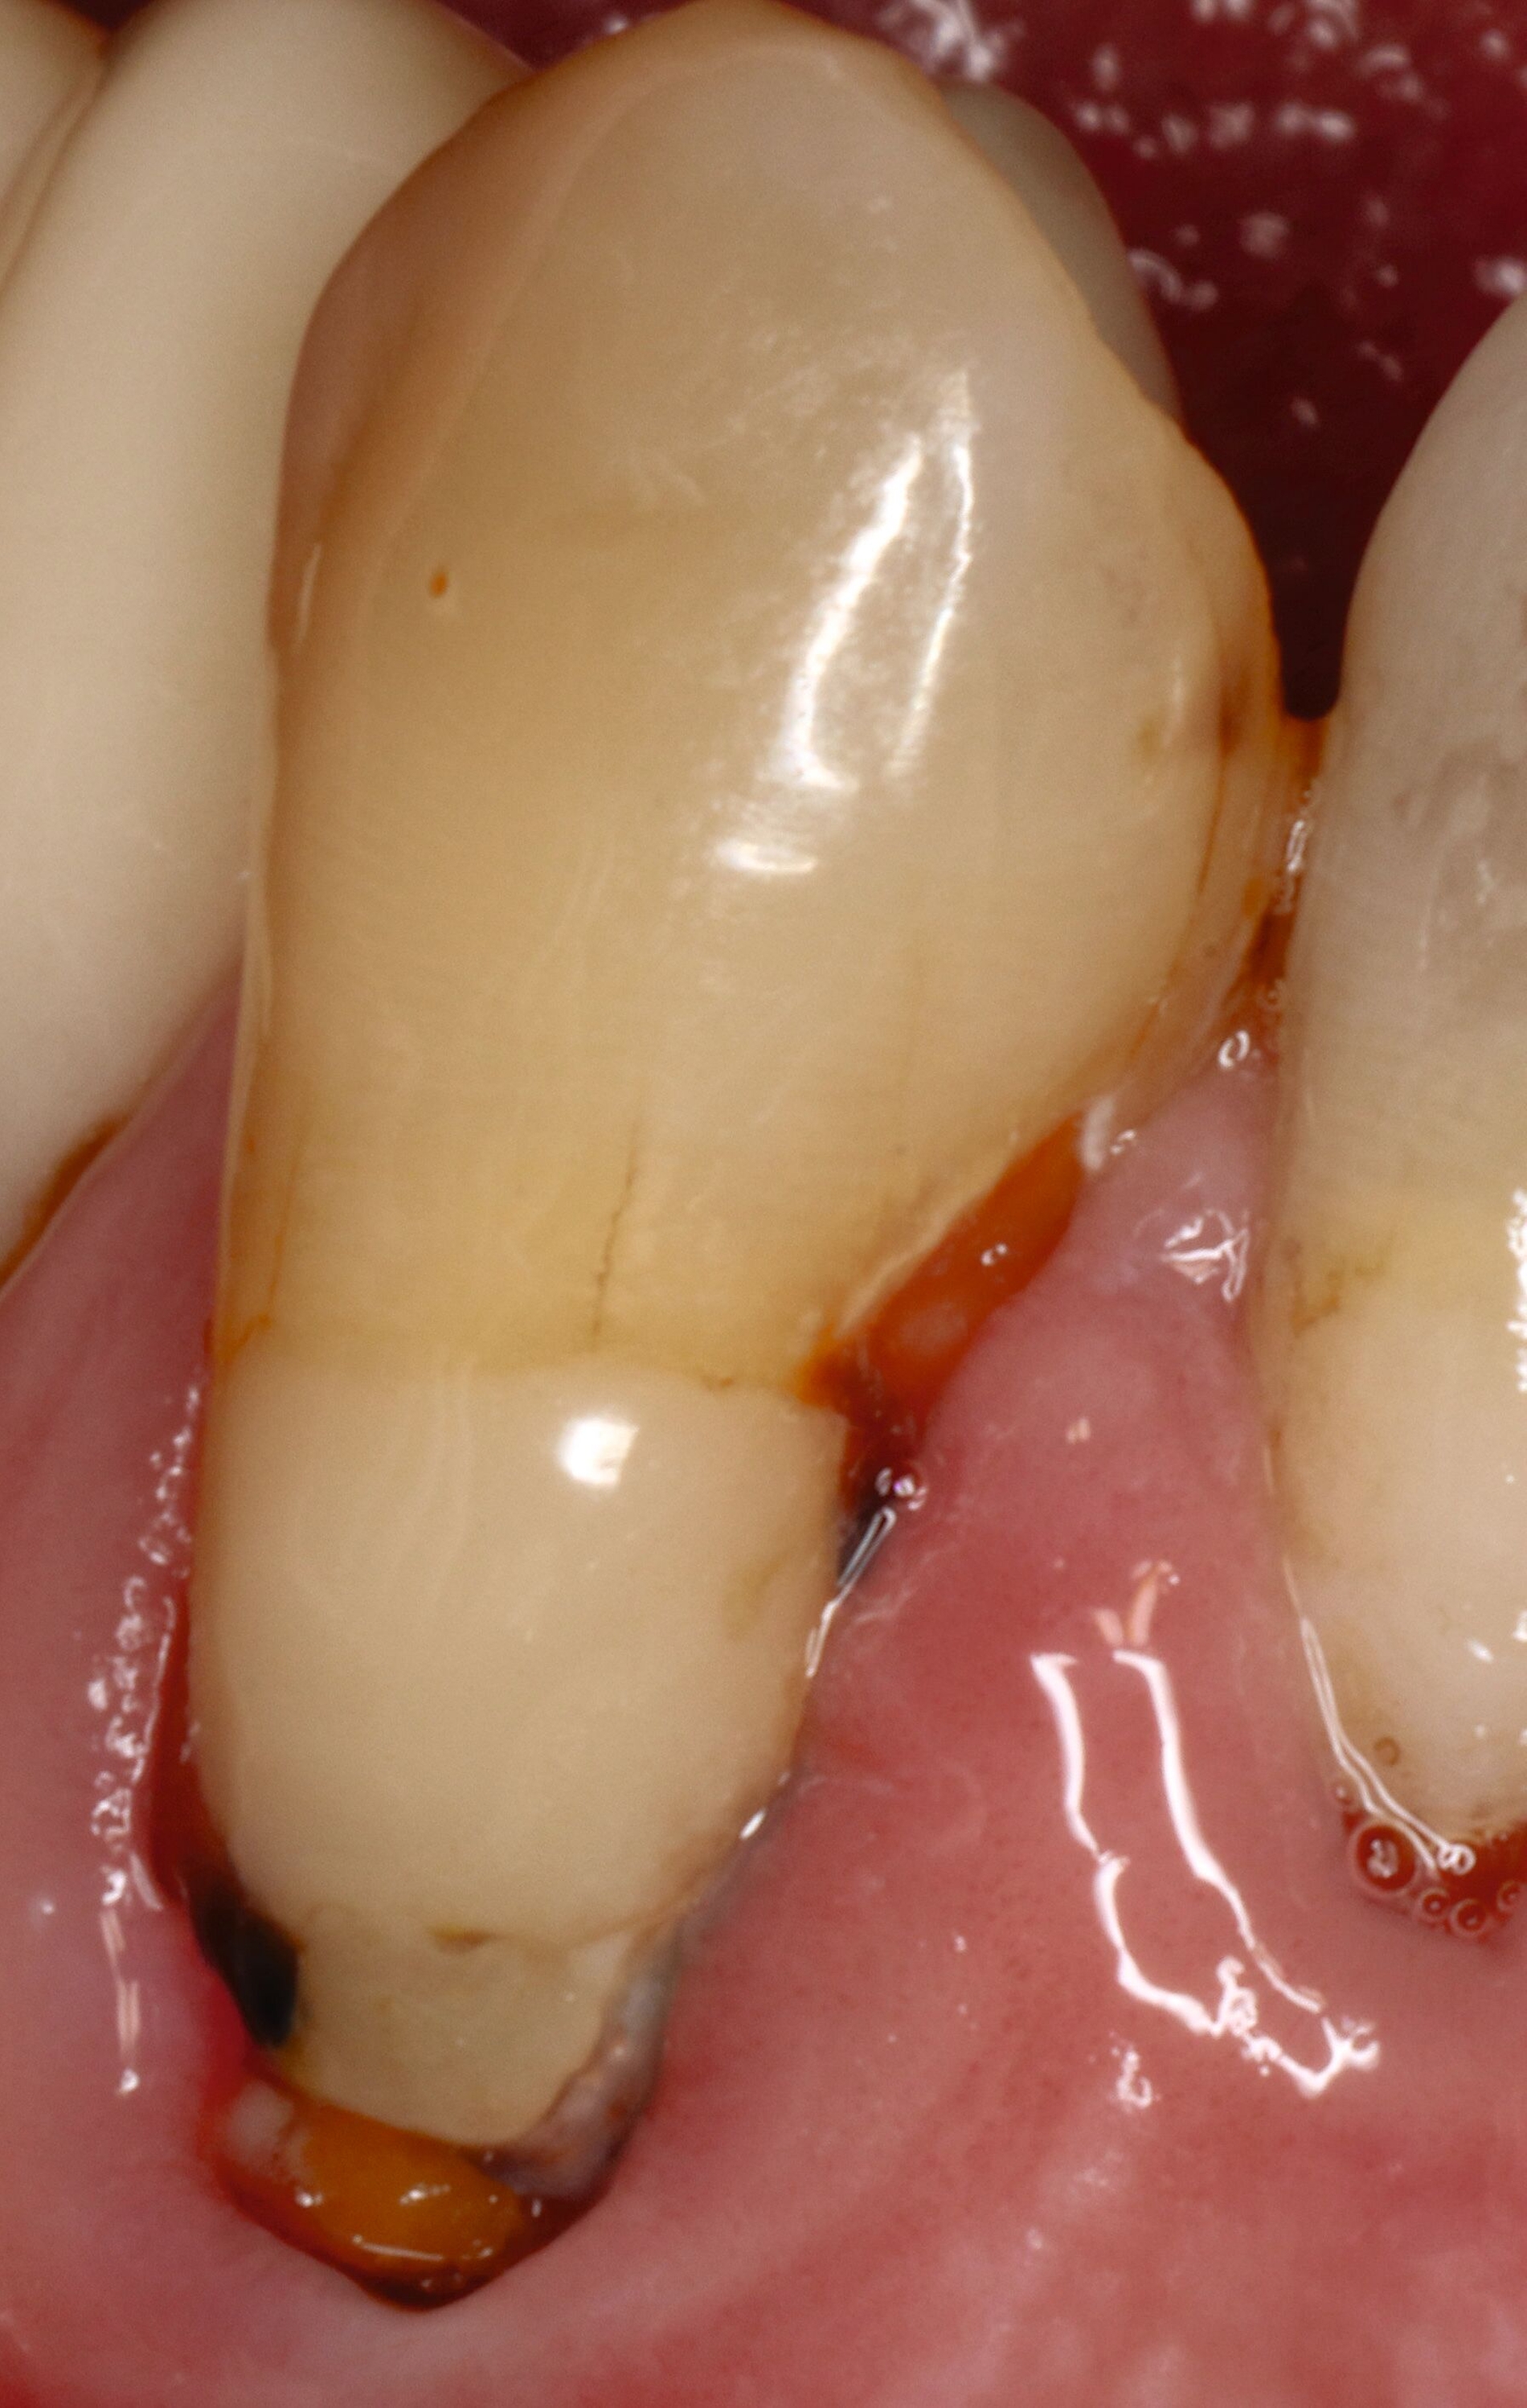

Wurzelkaries kann alle Bereiche der Wurzeloberfläche betreffen und ist in der Regel an Plaqueretentionstellen etwa im Bereich des Gingivarandes, der Kronenränder, der Einziehungen der Wurzeloberfläche oder des Interdentalraums lokalisiert. Zur klinischen Diagnostik sollte zunächst Plaque möglichst vollständig entfernt werden, um interdentale Bereiche einsehen und aussagefähig sondieren zu können. Während die Oral- und die Vestibulärflächen relativ einfach zu befunden sind, sollten die Interdentalräume unter guter Trockenlegung und Ausleuchtung beurteilt werden. Bei ausgedehnten Rezessionen ist die Diagnostik auch interdental gut möglich (Abbildung 4).

Für die Therapieentscheidung ist es essenziell, zwischen aktiven und inaktiven Läsionen zu unterscheiden (Abbildung 6). Die Farbe der Läsion ist zwar kein verlässliches Diagnosekriterium, aktive Wurzelkaries hat aber eher eine gelbliche oder hellbraune Farbe, ist in der Regel von Plaque bedeckt und fühlt sich bei mäßigem Sondieren weich oder ledrig an. Solche Läsionen bedürfen einer Intervention. Inaktive oder arretierte Läsionen haben in der Regel eine dunklere Farbe, sind meist plaquefrei und fühlen sich bei Sondieren hart an. Inaktive Wurzelkaries braucht keine weitere Intervention, auch wenn sie kavitiert, aber reinigungsfähig ist. Die Patientinnen und Patienten sollten jedoch über solche Befunde aufgeklärt werden.

Der Zugang zu approximalen Läsionen sollte, wenn immer möglich, von interdental versucht werden (beispielsweise im Fall von Abbildung 4). Wenn dies nicht möglich ist, erfolgt die Präparation von koronal, was jedoch oftmals erhebliche Opfer gesunder Zahnhartsubstanz erfordert. Die Versorgung der resultierenden tiefen approximalen Bereiche ist oftmals herausfordernd, zu den Behandlungstechniken sei auf die entsprechende Literatur verwiesen (beispielsweise [Muscholl, 2022]).